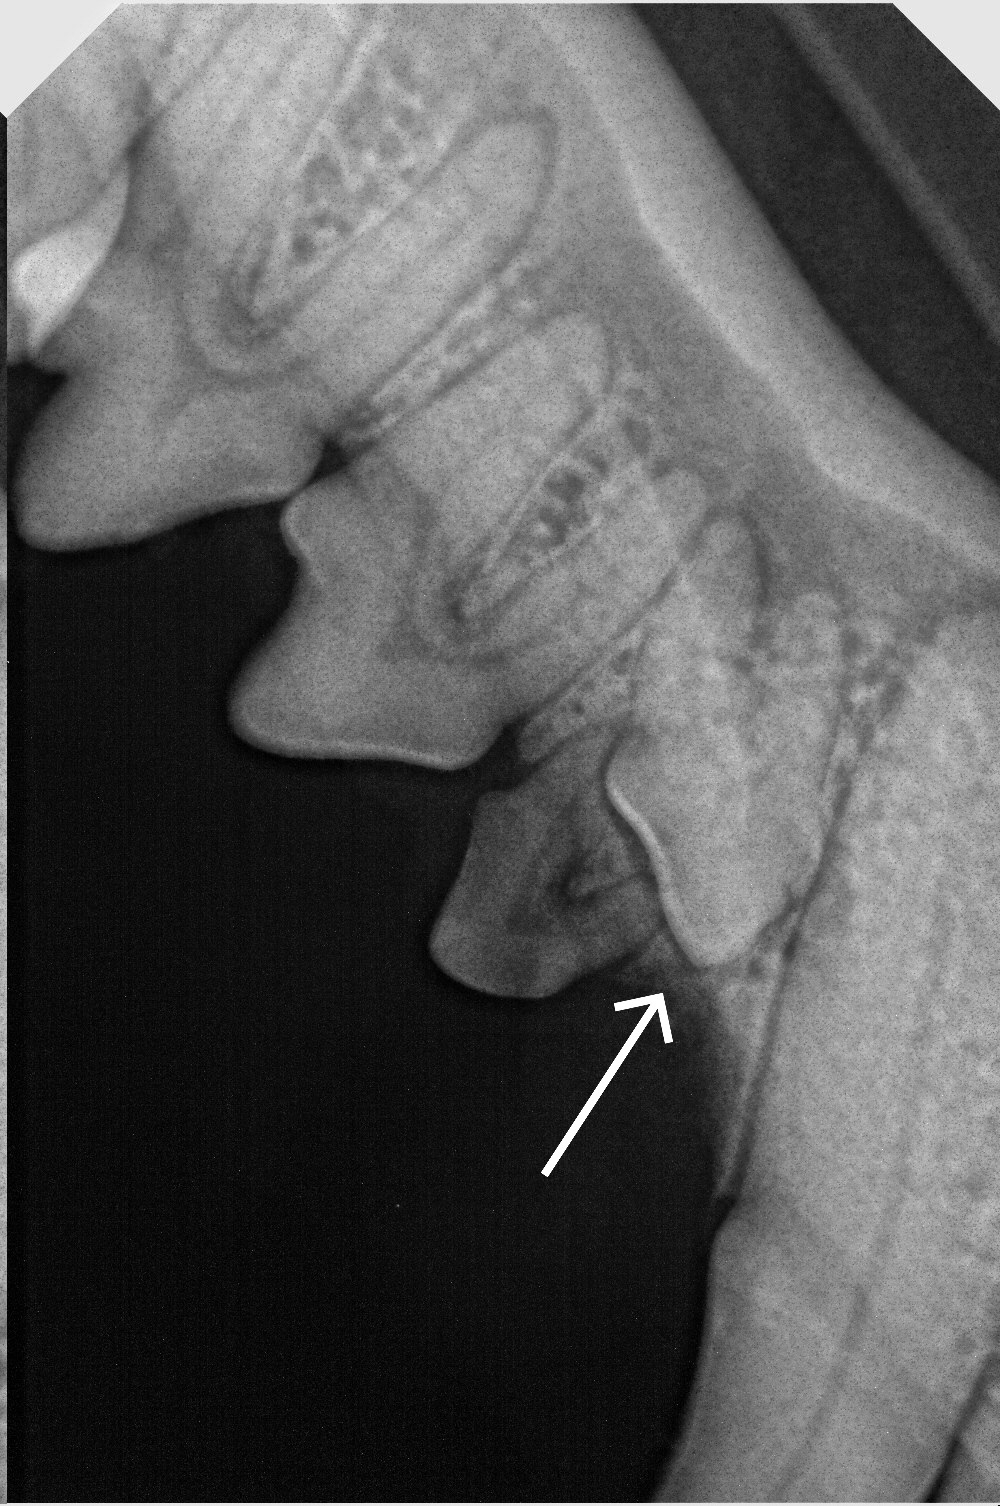

🩻Только благодаря рентгену и была установлена дополнительная патология в ротовой полости. У Тюли имелся ретинированный зуб, который не только доставлял боль и дискомфорт, но и мешал правильную развитию нижней челюсти.

Доктор Иван Ильич, провел удаление данного зуба, а также пластику тканей в области оставшейся лунки.